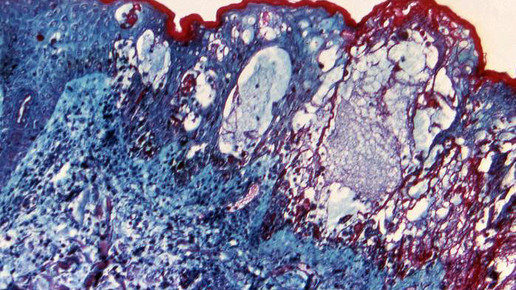

Seit Längerem ist ein Zusammenhang zwischen Gürtelrose und Windpocken bekannt. Der erste Kontakt mit dem Erreger Varizella zoster findet meist im Vorschulalter durch eine Tröpfcheninfektion statt. Nach etwa zwei Wochen entsteht ein juckender Ausschlag auf der Haut. Sind die Windpocken überstanden, wandern die Viren in die Hirnnerven und Nervenwurzeln des Rückenmarks. In den Nervenknoten verbleiben sie in einer Art „Schlaf“. Werden sie durch Stress, UV-Strahlung, ein schwaches Immunsystem oder durch das erreichte höhere Alter reaktiviert, entsteht eine Gürtelrose. Die Reinfektion tritt lokal begrenzt beispielsweise an Brust, Bauch, Rücken oder Kopf auf. Besonders gefährlich kann es werden, wenn die Viren in Auge oder Ohr eine Gürtelrose hervorrufen.